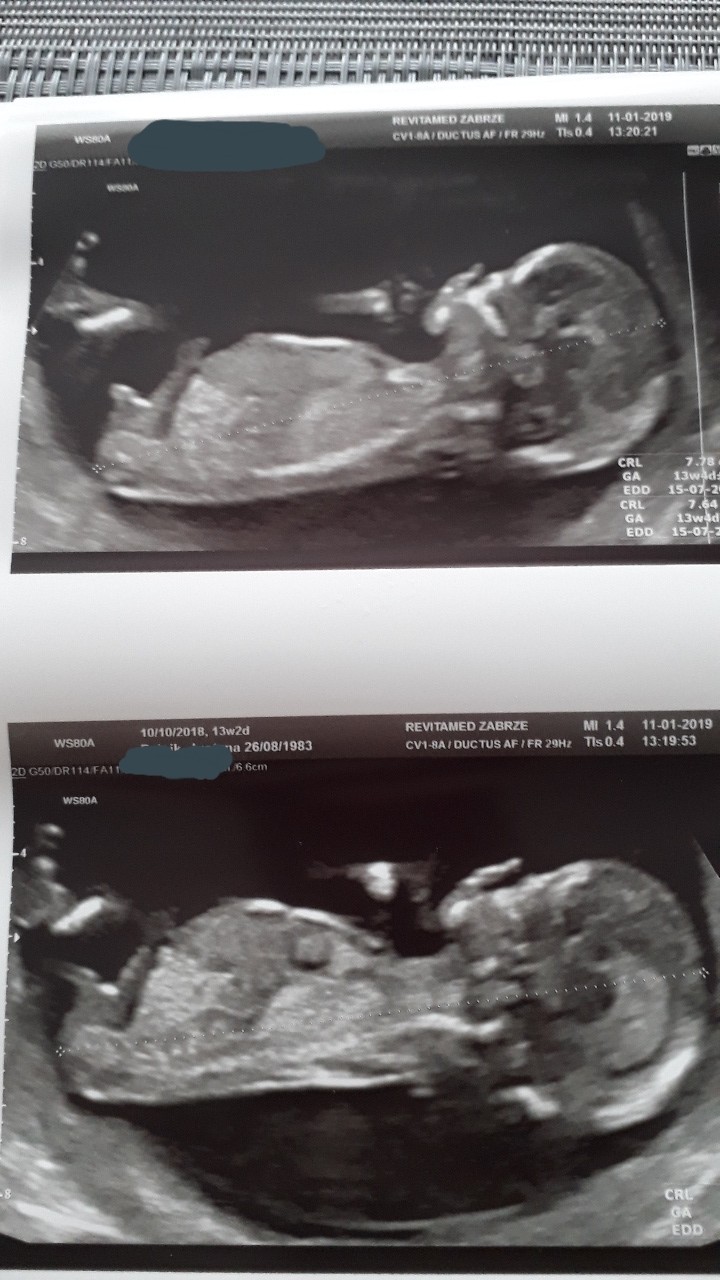

, a to 14 tyg + 5dni, nocki też rzadko przespane się zdarzają. Co polecacie na przeziębienie, bo jakoś tak od rana czuję się niewyraźnie